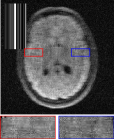

MRI We evaluate on the fastMRI brain validation set using the single-coil accelerated acquisition procedure from Zbontar et al. (2018) with acceleration factors and . The problem is formulated as , where is a binary mask and the discrete Fourier transform, and . Quantitative results are reported in Table 2 and visuals in Figure 7. The proposed RAM model outperforms all baselines.

Single coil MRI

We provide in Figure 7 visual results for MRI reconstructions on acceleration factors 4 and 8 respectively.

Multi-coil MRI

We provide in Figure 9 results on the multi-coil MRI inverse problem where we simulate coil maps. The UNet reconstruction shows a less smooth aspect, penalizing PSNR.

| uDPIR tied | RAM | Ground-truth | ||

| acc. factor 4 | ![]() |

![]() |

| 0.863 | 0.868 | SSIM | ||

| acc. factor 8 | ![]() |

| 0.831 | 0.840 | SSIM |